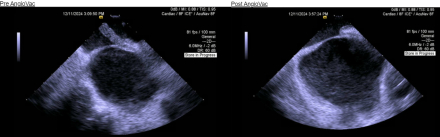

A 58 year old man with non-ischemic cardiomyopathy (LVEF 21%) secondary to presumed (non-biopsy proven) cardiac sarcoidosis on prednisone and infliximab status post CRT-D placement, recurrent admissions for VT, and CKD presented to the emergency room with right upper quadrant pain. Chest x-ray revealed right lower lobe pneumonia and he was started on broad-spectrum antibiotics. He was admitted to the ICU and rapidly developed severe acute hypoxemic respiratory failure requiring intubation, maximum ventilator support, and neuromuscular paralysis. He concomitantly developed severe shock requiring high doses of three vasopressors. In this setting, he had hemodynamically unstable runs of monomorphic VT treated with IV amiodarone and lidocaine. He suffered a VT arrest (Image 1), with rates below his device detection zone, and was externally defibrillated.